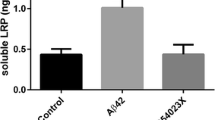

Effect of MMP9 Inhibition on Lipoprotein Receptor Shedding and Aβ Clearance In Vivo

In line with our findings in vitro and ex vivo, treatment with the MMP9 inhibitor, SB-3CT, significantly reduced (> 2-fold) soluble LRP1 and LDLR levels in the brains of apoE4-TR animals compared with vehicle-treated apoE4-TR mice (Fig. 6). With respect to brain Aβ elimination, apoE4-TR mice treated with the SB-3CT showed a significant increase in the appearance of Aβ in the plasma following intracranial monomeric Aβ administration (2-fold) compared with apoE4-TR mice treated with vehicle (Fig. 7), indicating enhanced Aβ elimination across the BBB upon MMP9 inhibition. Interestingly, the extent of Aβ BBB elimination in the apoE4-TR mice treated with SB-3CT was the same as that observed in the apoE3-TR animals (Fig. 7). Lastly, we also probed the plasma for the appearance of GFAP in each of the mice from SB-3CT study in addition to age-matched naïve mice (i.e., no intracranial Aβ injection). Moreover, as a positive comparison, we examined GFAP in the plasma of E4FAD mice, which express five familial AD mutations (5xFAD) alongside the targeted replacement of human apoE [31]. The E4FAD mice have been shown to exhibit BBB dysfunction and cerebrovascular leakiness [32]. In our studies, we did not observe differences between any of the groups of mice in the appearance of GFAP in the plasma, when compared with the respective apoE3 naïve group (Fig. 8). Of note, no statistically significant difference in lipoprotein receptor shedding or Aβ elimination across the BBB was observed between the male and female cohorts in these studies.

Levels of LRP1 and LDLR in the soluble brain fraction of apoE transgenic mice following treatment with a MMP9 inhibitor, SB-3CT. Vehicle or SB-3CT (25 mg/kg) was administered i.p. to apoE4-TR mice and, after 45 min, human Aβ(1–42) was injected intracranially. Ten minutes after the intracerebral injection, the brains were collected and various brain fractions were isolated. LRP1 or LDLR levels in the soluble brain fraction were determined using an ELISA. Values represent mean ± SEM (n = 4) and are expressed as ng of LRP1 or LDLR per ml of soluble brain material. *P < 0.05 compared with respective vehicle as determined by ANOVA and Bonferroni post hoc test